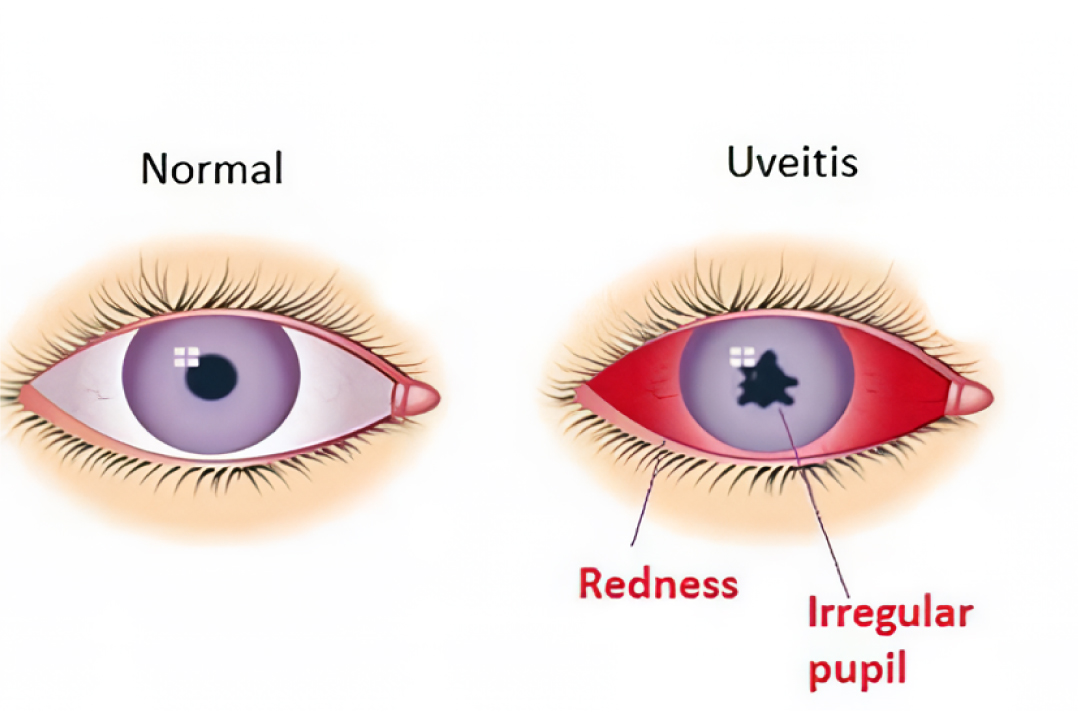

葡萄膜炎

葡萄膜炎,即眼球中层葡萄膜的炎症,是一种常见的、可能威胁视力的眼科疾病,其病因复杂且常常不明,包括感染、自身免疫性疾病、损伤和毒素等。根据炎症发生的部位,临床上可将其分为前葡萄膜炎、中间葡萄膜炎、后葡萄膜炎和全葡萄膜炎等。该炎症表现为眼睛发红、疼痛、视力模糊、畏光和飞蚊症等症状。

中医将此眼疾描述为“瞳神紧小”或“瞳神干缺”,认为其病因病机复杂多样。外感风热侵袭肝脏,或肝郁化火导致肝胆火旺,热邪上犯黄仁(虹膜),使之受损,表现为瞳孔无法正常收缩。外感风湿蕴积化热,熏蒸黄仁,亦可致病。此外,肝肾阴虚或久病伤阴,虚火上炎,黄仁失养,加上虚火煎灼,导致瞳孔紧小或收缩失灵,甚至与晶状体粘连形成瞳神干缺。简而言之,此病由外邪侵袭、脏腑失衡、阴液亏虚等多种因素共同作用,导致黄仁功能障碍。

西医主要依赖皮质类固醇,有时辅以非甾体抗炎药或免疫抑制剂,以控制这些症状并预防青光眼、白内障和视力丧失等严重并发症。然而,长期或高剂量使用皮质类固醇可能导致代谢紊乱和肾上腺功能不全。因此,结合中医进行全身调理可以减轻这些副作用,增强调理效果,并减少复发。疗程通常需要持续10个月以上,直至炎症完全消退。